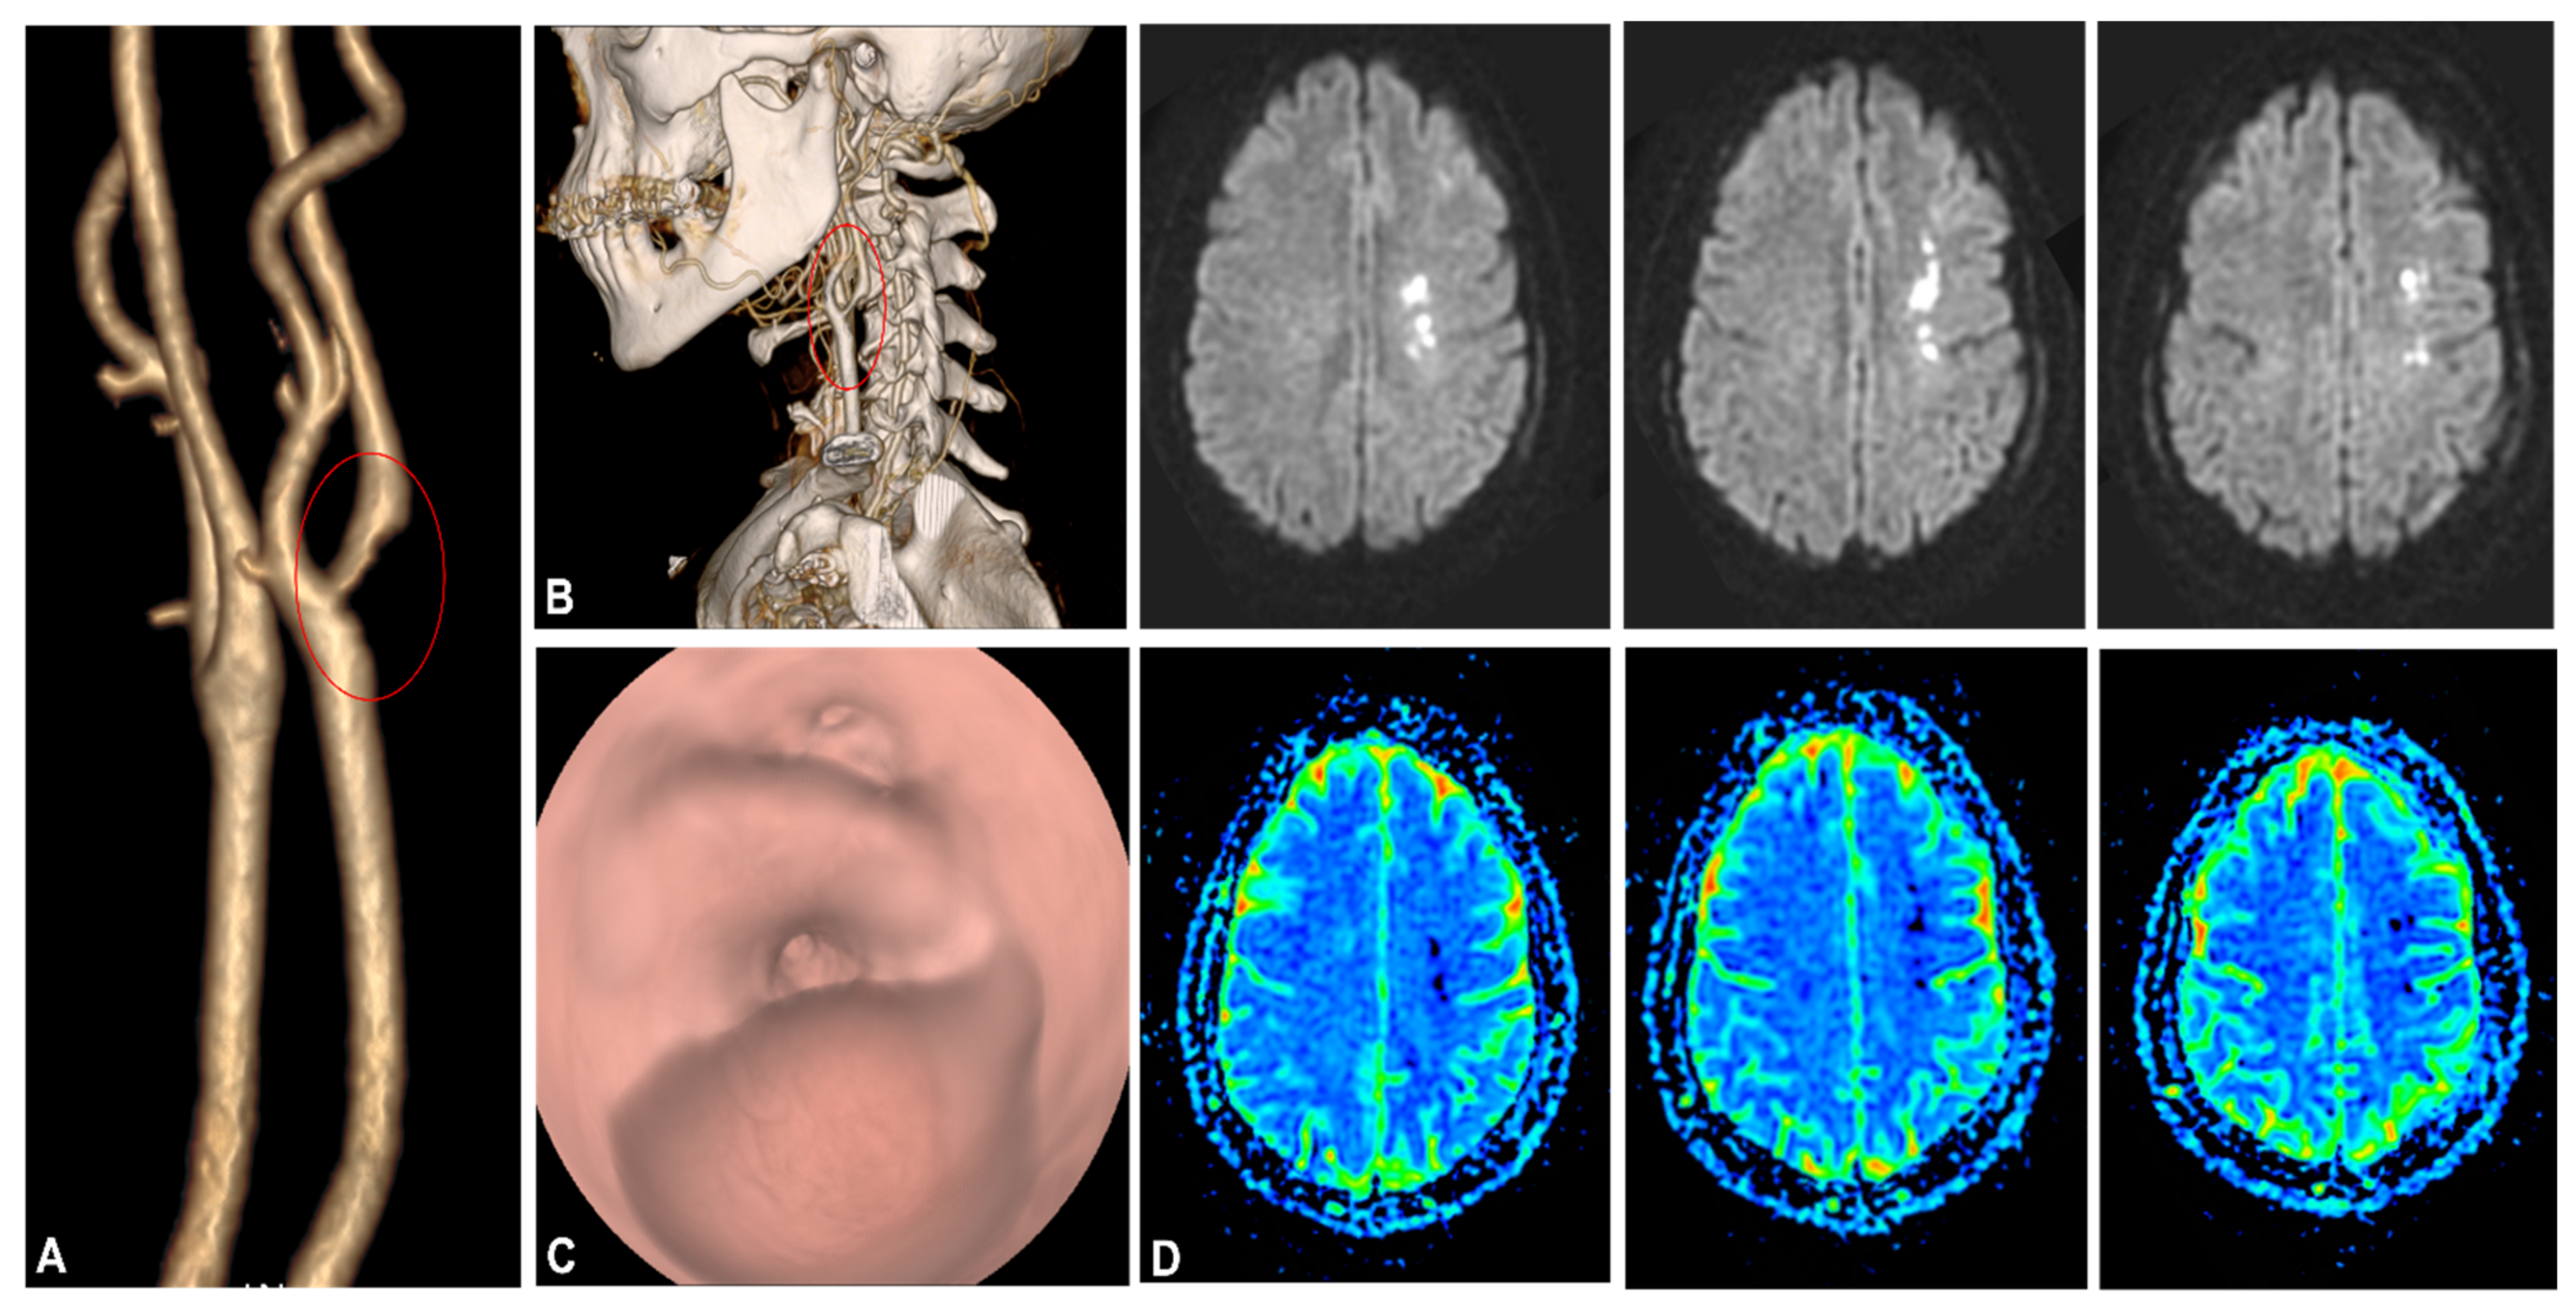

- Wang, A.; Mandigo, G.K.; Yim, P.D.; Meyers, P.M.; LaVine, S.D. Stroke and mechanical thrombectomy in patients with COVID-19: Technical observations and patient characteristics. J. NeuroInterv. Surg. 2020, 12, 648–653. [Google Scholar] [CrossRef]

- Viguier, A.; Delamarre, L.; Duplantier, J.; Olivot, J.-M.; Bonneville, F. Acute ischemic stroke complicating common carotid artery thrombosis during a severe COVID-19 infection. J. Neuroradiol. 2020, 47, 393–394. [Google Scholar] [CrossRef]

- Fara, M.G.; Stein, L.K.; Skliut, M.; Morgello, S.; Fifi, J.T.; Dhamoon, M.S. Macrothrombosis and stroke in patients with mild Covid-19 infection. J. Thromb. Haemost. 2020, 18, 2031–2033. [Google Scholar] [CrossRef]